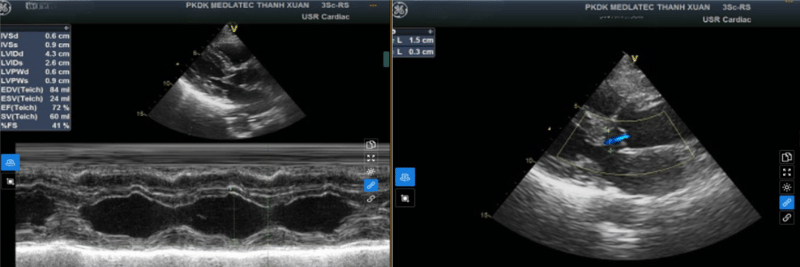

Siêu âm Doppler hệ thống động mạch cảnh và động mạch đốt sống phần ngoài sọ phát hiện mảng xơ vữa vôi hóa tại xoang cảnh trái, gây hẹp lòng mạch không đáng kể. Siêu âm tim ghi nhận hở nhẹ van động mạch chủ.

Siêu âm Doppler hệ thống động mạch cảnh và động mạch đốt sống phần ngoài sọ cho thấy mảng xơ vữa vôi hóa tại xoang cảnh trái

Kết quả siêu âm tim của bà C.